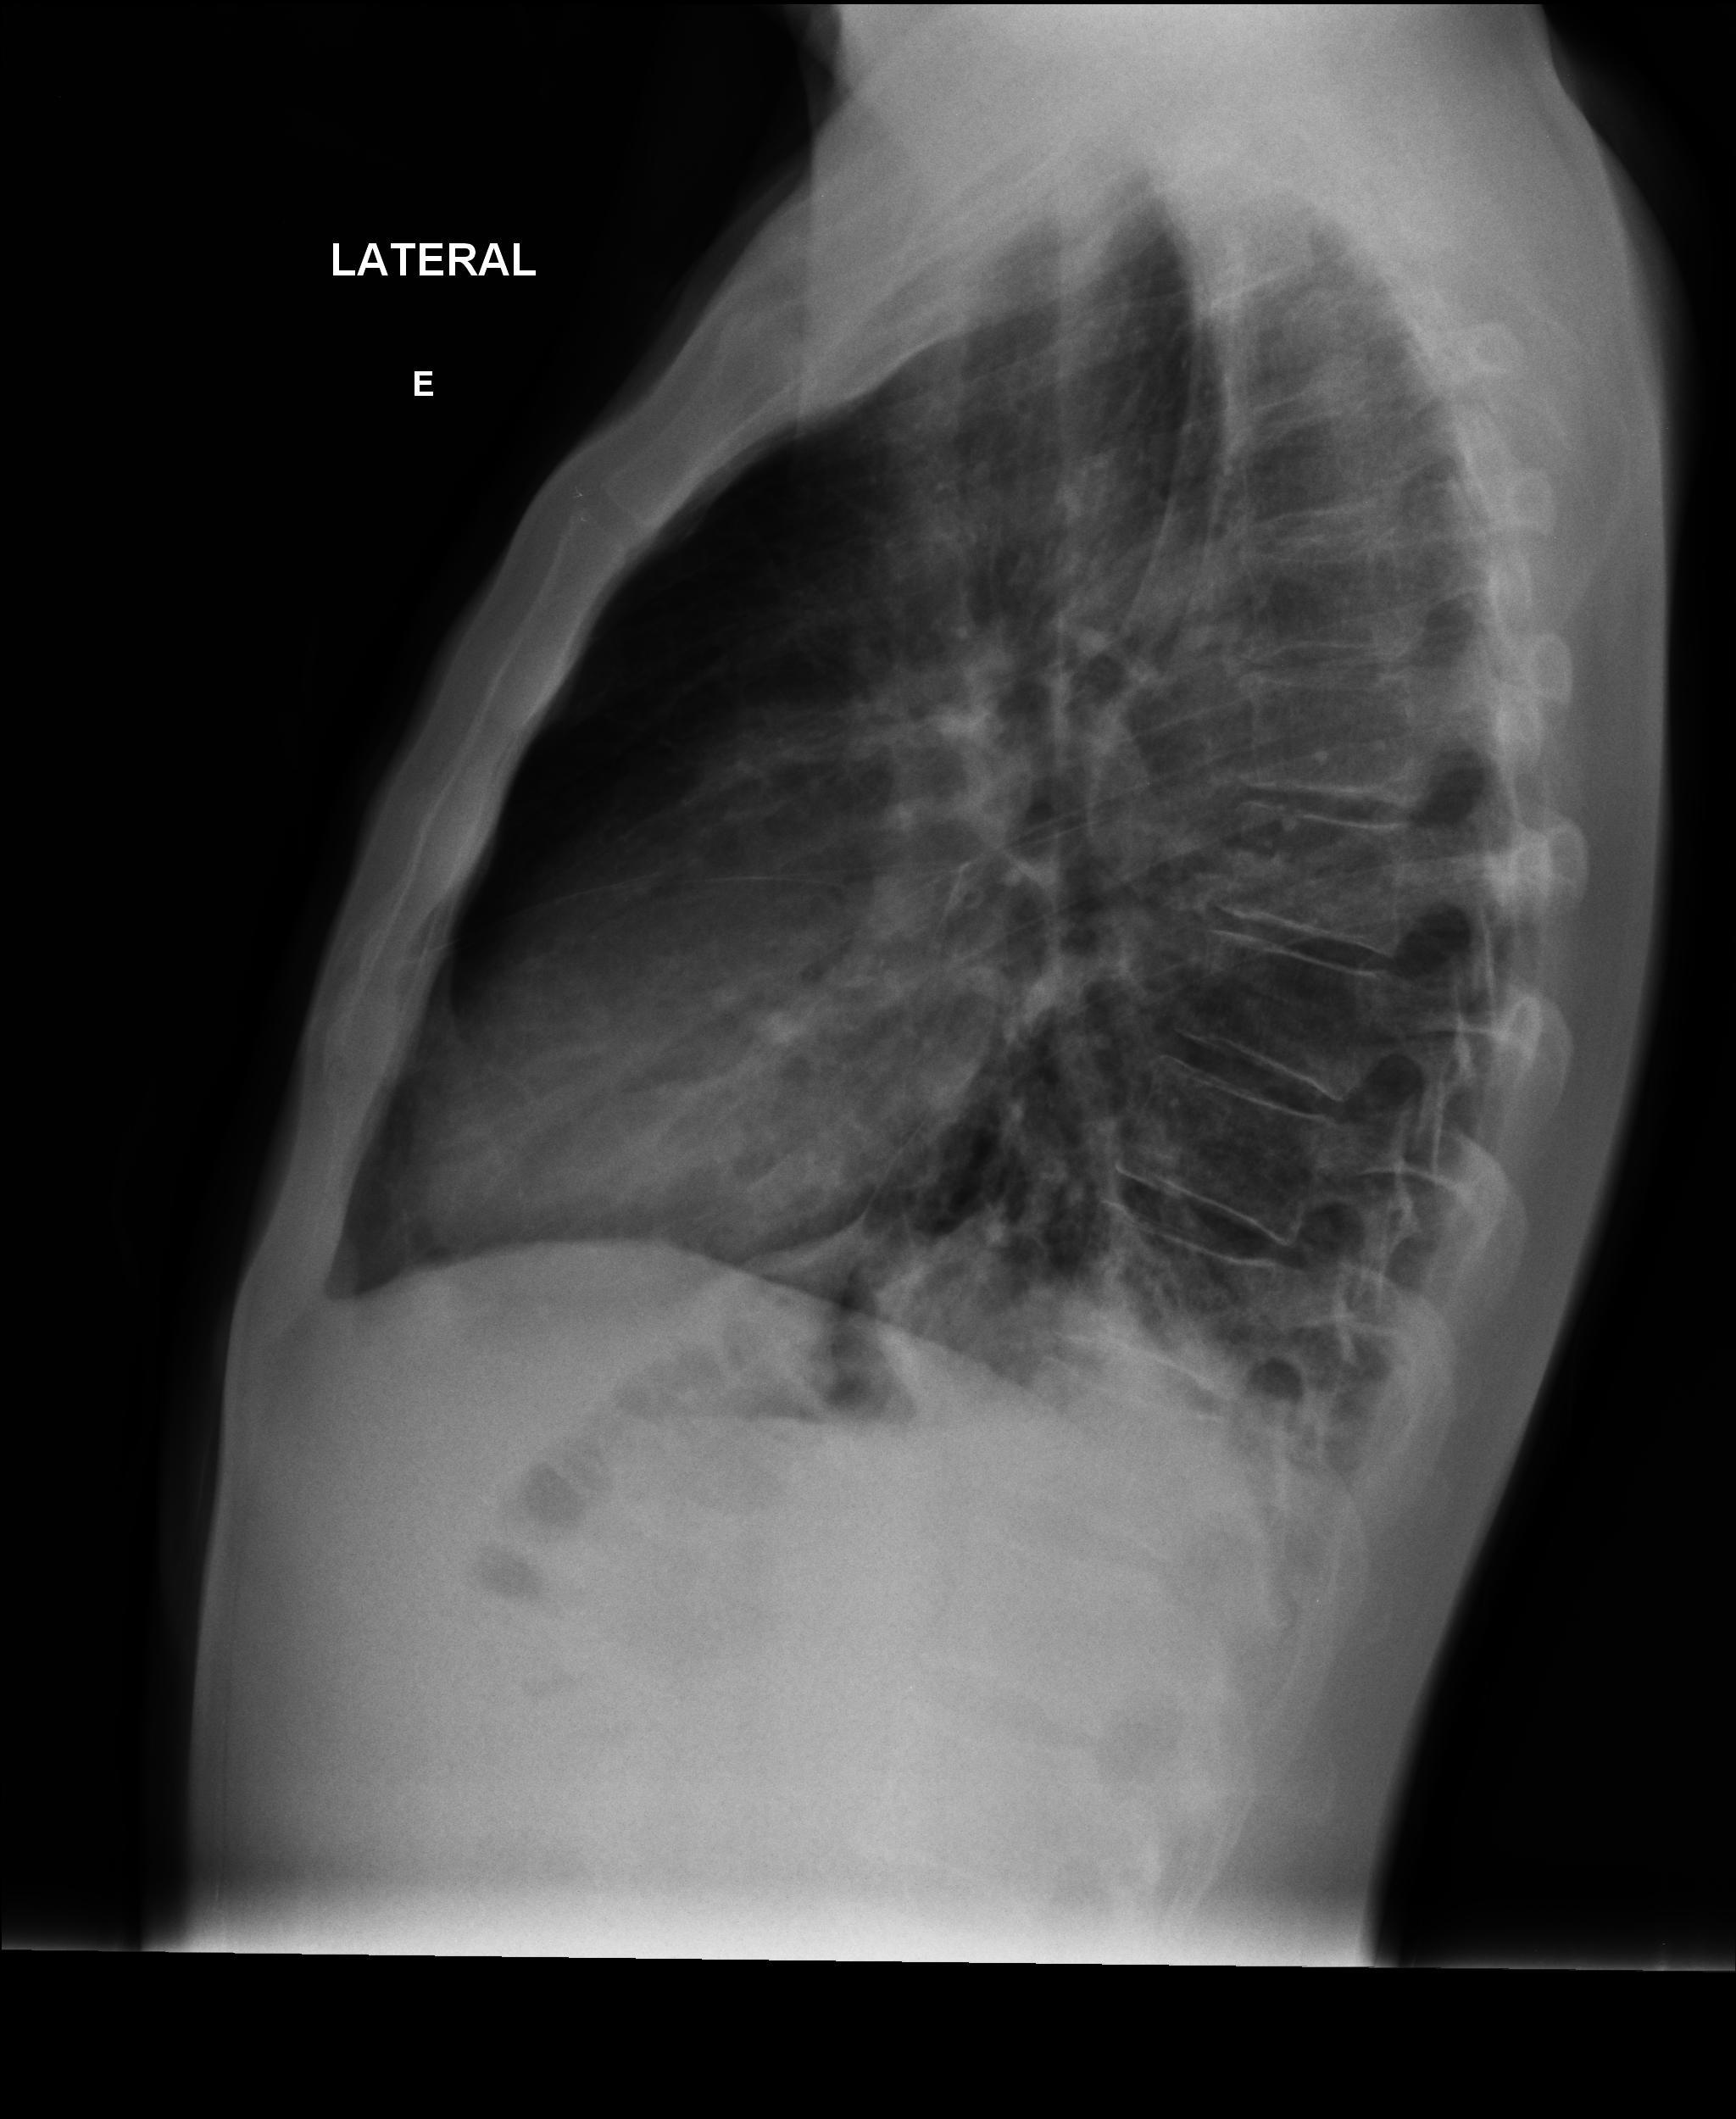

Caso relatado na Reunião de Discussão de Casos Clínicos do Hospital Universitário Prof. Polydoro Ernani de São Thiago, iniciada pelos Profs. Jorge Dias de Matos, Marisa Helena César Coral e Rosemeri Maurici da Silva, em julho de 2017. No dia 14 de junho de 2018, no auditório do HUPEST, realizou-se a apresentação e discussão do caso cujo registro é apresentado a seguir. Trata-se da discussão de onze casos em radiologia torácia, de forma interativa com a plateia, e assim ocorre também neste artigo.